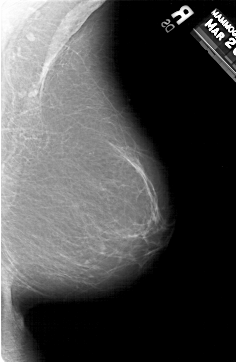

A_1308_1.LEFT_MLO

LEFT_MLO LINES 5986 PIXELS_PER_LINE 3841 BITS_PER_PIXEL 12 RESOLUTION 43.5 OVERLAY